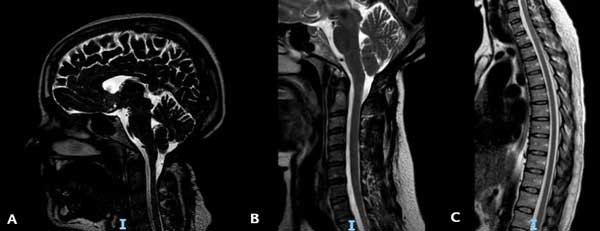

La RM de control realizada en octubre 2023 mostró un ascenso de las amígdalas cerebelosas y una resolución completa de la siringomielia (Figura 5). Actualmente sigue bajo control y solo persisten una leve hipoestesia en la mano izquierda y parestesias en la región subescapular izquierda.

Figura 5. RM ponderada en T2 en la que se observa: A) El ascenso amigdalino. B) La resolución de la siringomielia cervical. C) La resolución de la siringomielia torácica.